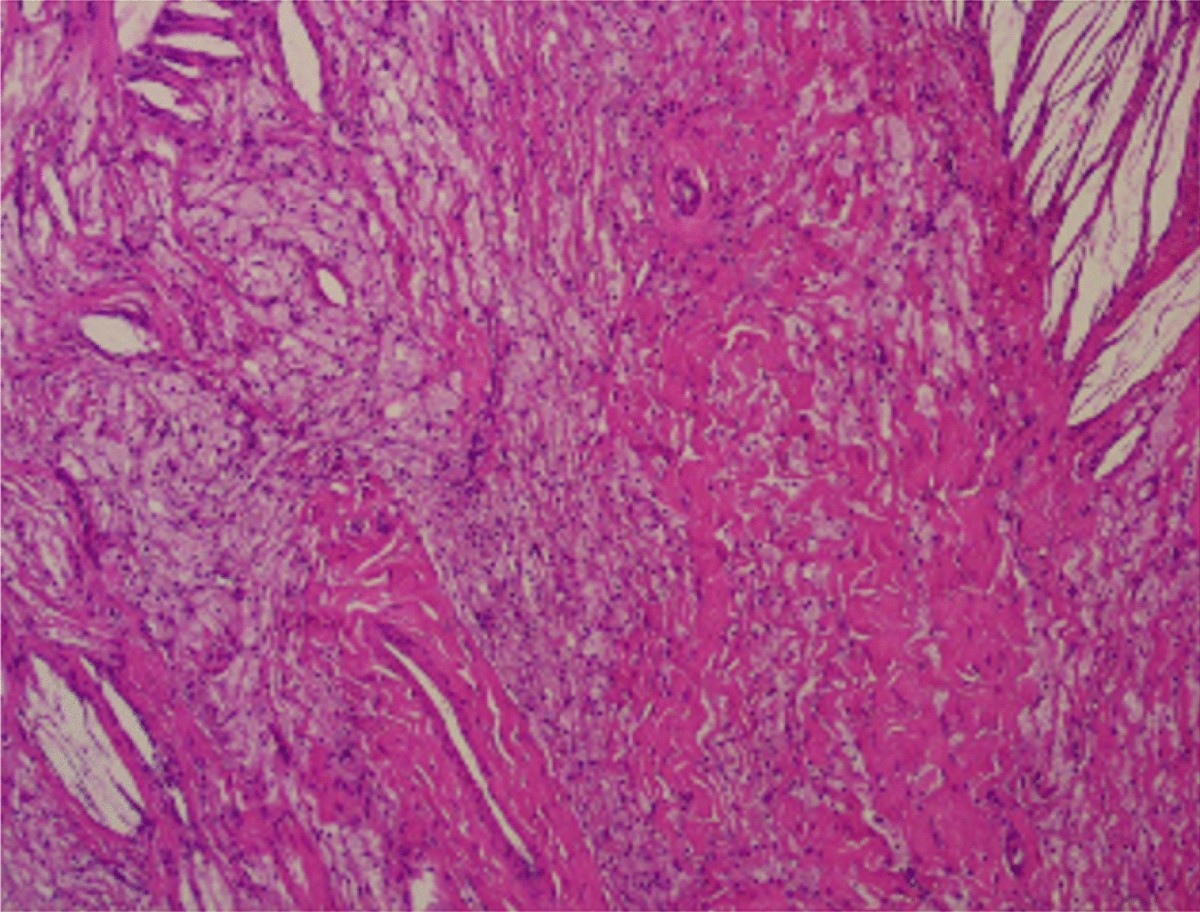

Pathology Outlines - Xanthoma